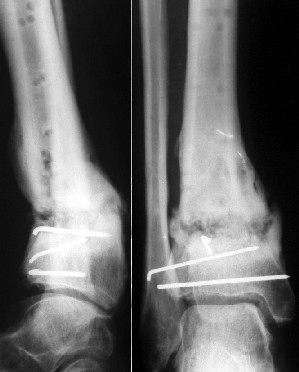

Операции: 1 Клиновидная резекция на вершине деформации м\берцовой кости.

2 Тугоподвижный ложный сустав н\3 б\берцовой кости. Рубцы выполняющие пространство между отломками, канал проксимального отломка иссечены.

Одномоментное устранение деформации, остеосинтез Г-образной пластиной.

Пластика по Хахутову.

Заживление проксимальной части раны вторичным натяжением без нагноения. Рана зажила. Спицы удалены через 1,5 недели после операции.

Учитывая фон (интеллект, etc) гипсовая повязка.

На данный момент ходит при помощи костыля (без присмотра -без костыля :), разрабатывает движения в г\стопном суставе.